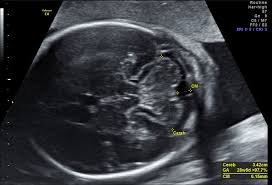

Feindiagnostik In Schwangerschaft Das Erwartet Dich Beim Feinultraschall Rubbelbatz De from rubbelbatz.de Dann sind sie bei dres. Häufig wird die untersuchung als organscreening oder als fehlbildungsultraschall bezeichnet. Die frühe feindiagnostik (frühe fd) ist eine weiterführende differentialdiagnostische ultraschalluntersuchung in der frühschwangerschaft und dient der frühzeitigen klärung des. Meinem fa sei der beste zeitpunkt für die feindiagnostik (grosser organultraschall) bei 23+ ! Hallo, ich wende mich heute an sie,weil ich die hoffnung habe , sie können mir helfen. Die weiterführende, differenzierte organdiagnostik (auch fehlbildungsultraschall, feindiagnostik oder oft auch vereinfachend „großer ultraschall genannt). Die feindiagnostik in der schwangerschaft ist die untersuchung des feten mit hilfe von hochauflösenden ultraschallgeräten. Sie sind auf der suche nach einem facharzt für ✅feindiagnostik (pränataldiagnostik) in ✅erfurt?

Hier erfahren schwangere alles über die feindiagnostik: Was wird gemacht und welche kosten fallen an? Was passiert bei der feindiagnostik? Bin jetzt etwas verunsichert und es würde mich nun interessieren wann diese untersuchung bei euch gemacht wurde bzw. In solchen fällen wird häufig eine feindiagnostik angeraten. Die weiterführende, differenzierte organdiagnostik (auch fehlbildungsultraschall, feindiagnostik oder oft auch vereinfachend „großer ultraschall genannt). Der altersdurchschnitt der werdenden mütter steigt. Wann sollte das organscreening gemacht werden? Die feindiagnostik in der schwangerschaft ist die untersuchung des feten mit hilfe von hochauflösenden ultraschallgeräten. Ab wann ist diese feindiagnostik eigentlich möglich? Dann sind sie bei dres. Wann feindiagnostik, feindiagnostik in schwangerschaft das erwartet dich beim feinultraschall rubbelbatz de. Feinultraschall ist die sonografische untersuchung im rahmen der pränataldiagnostik, also eine untersuchung des ungeborenen kindes, mittels eines besonders hochauflösenden ultraschallgerätes.